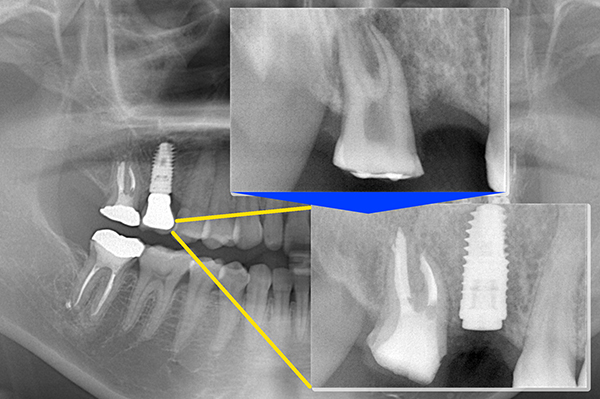

当院では安心安全なインプラント治療をより確実に行うために、すべてのインプラント治療で3Dコンピューターシミュレーションシステム「シンプラント プロ」で歯科CT画像からデータ解析を行い、サージガイドを作成するコンピューターガイデッド インプラント治療を行っています。

シンプラント プロとは

一般的なレントゲン写真のみでの術前診断では、平面的な写真画像のため、骨の厚みや神経の走行などを立体的に見ることはできませんでした。

そのため手術中に骨の状態を直接見て手術を行う必要があり、術者の経験や勘頼りになりやすく計画していた位置にインプラント手術が行えないということもあります。

歯科用CTは、顎の骨の断面像を見ることができ、一般的なレントゲン写真よりも多くの情報を得ることが可能です。しかし、実際の手術ではそのCT画像を参考にして、フリーハンドでインプラント手術を行うため、やはり術者の経験や勘頼りになりやすく計画した位置からずれてしまうこともあります。

シンプラント プロのコンピューターガイデッド インプラント治療では、歯科CT画像から3D画像を構築し、骨の厚みや神経の走行などを視覚的に診査できます。

そして嚙み合わせ、骨の厚みや神経の走行からからみて三次元的に理想的なインプラントの位置を画像上でシミュレーションすることができます。これにより手術を行う前に安全で理想的なインプラントの位置を決定することが可能になりました。

画像は患者様に見てもらうことで予定するインプラントの施術後のイメージを画像で確認できます。

歯科CTデータからシンプラントで3D画像を表示して骨の厚みや神経、血管の走行を検査します

噛み合わせ、骨の厚みや神経の走行からみて理想的なインプラントの位置を決定

インプラント治療の仕上がりのイメージは画像で患者様も視覚的に確認できます

コンピューターガイデッド インプラント治療とは

「シンプラント プロ」で計画されたシミュレーションデータからサージガイドを作製します。

作製されたサージガイドをお口の中に装着して手術を行うことにより、計画した位置をお口の中に正確にトランスファーしてインプラント手術することができます。

サージガイドを使用することで、狭く小さいお口の中や手術しにくい奥歯でも精度の高い正確なインプラント治療が行うことが可能です

コンピューターガイデッド インプラント治療では、歯科医師の経験にプラスして手術の精度もよく、安心安全なインプラント治療をより確実に行うことができます。

右下の奥歯の失った部位に対して、痩せた歯茎の再生治療とインプラント治療を行いました。

症例2

痩せてしまった下顎の骨を再生させる手術と歯茎を再生する手術を行い、3本のインプラント治療を行いました。